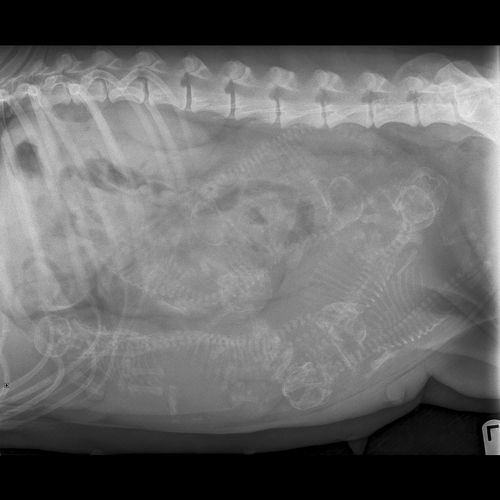

10/2/12 - Puppies are here!!!! Cordie went into labor this am and easily whelped 6 puppies and then everything just "stopped". So we took her immediately to the vet and we did an emergency c-section. Unfortunately, we were not able to save the last two puppies and it just broke my heart. But....I am sure that those two puppies are with Kim in heaven and are keeping her company. She was so excited for these puppies... The good news is that the remaining six puppies are doing great!! They are nursing really well and Cordie is a fantastic mom. Even after whelping and having surgery she never lets the puppies out of her sight. I have posted some pictures below....enjoy the puppy breathe - I sure am!!!